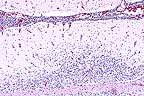

Non suppurative meningoencephalitis in an Appaloosa gelding infected with equine lentivirus (HE, 100X, 76K)

Contributor's Diagnosis and Comments: Severe nonsuppurative meningoencephalitis and choroid-plexitis with microgliosis. Lentivirus of equine infections anemia (EIA).

This case represents a classic presentation of the neural form of EIA. In the contributors experience, less than 2% of Coggin's positive horses have evidence of CNS involvement. This horse had typical gross lesions of recrudescing EIA. The farm of origin has had problems in the past with EIA and this case caused a quarantine to be placed on the farm.

The CNS lesion typically has an "inside out" pattern, whereby the inflammation is severe around the ventricular system. In this horse, that was best seen in the spinal cord. This horse tested negative for sarcocystosis, neosporsosis, VEE and EEE.

AFIP Diagnosis: Cerebellum, brain stem, midbrain, and choroid plexus: Choriomeningoencephalitis, nonsuppurative, multifocal, moderate, Appaloosa, equine.